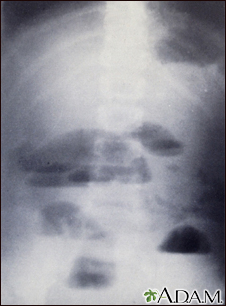

Small bowel obstruction - x-ray